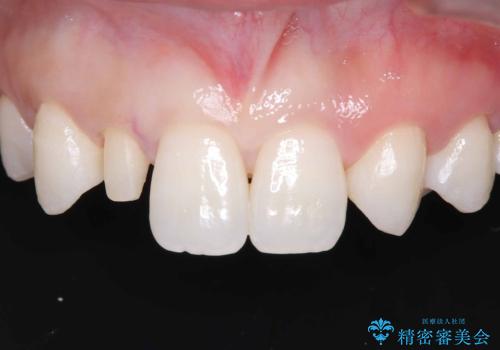

- 「前歯の見た目が気になる」を主訴に来院された患者様です。

右上2が矮小歯だったので、オールセラミッククラウンで審美修復しました。